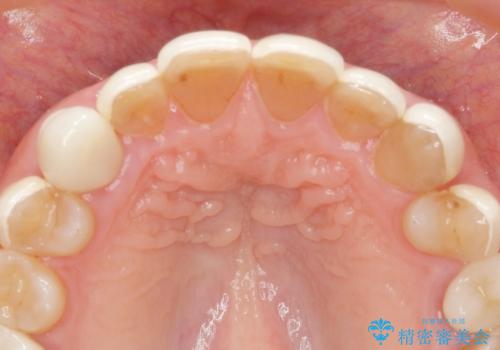

ラミネートを丁寧に除去したのち、ジルコニアクラウンを作製し審美性の回復・向上を計画します。

- 88万円(仮歯・ジルコニアクラウン×8)費用は治療当時の料金となります